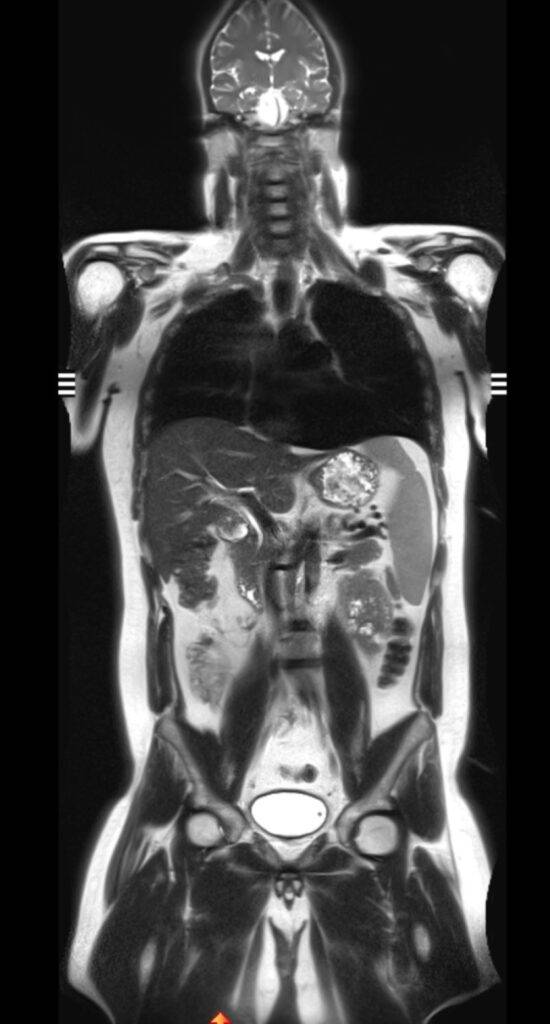

Eine Ganzkörper MRT liefert hochauflösende Bilder des gesamten Körpers von Kopf bis Fuß und ist daher ideal für Vorsorgeuntersuchungen oder zur Verlaufsbeurteilung von malignen Erkrankungen:

- Wurde bereits eine Tumorerkrankung diagnostiziert, kann die Ganzkörper MRT nützlich sein, die momentane Ausbreitung präzise zu beurteilen. Auch Fernmetastasen können durch eine Ganzkörperuntersuchung frühzeitig festgestellt werden. Die MRT ist aufgrund des höheren Weichteilkontrasts speziell in den Organen des Oberbauchs, der Lymphknoten, des Gehirns und des gesamten Skelettsystems hochpräzise bei der Erkennung von Metastasen.

- Auch zur Verlaufsbeurteilung und zur frühzeitigen Erkennung von Rezidiven bei malignen Erkrankungen eignet sich die Ganzkörper MRT hervorragend.

Die Ganzkörper-MRT stellt eine besonders detaillierte Methode in der medizinischen Bildgebung dar, die es ermöglicht, ohne die Verwendung ionisierender Strahlung, das Innenleben unseres Körpers umfassend zu visualisieren. Mittels starker Magnetfelder und Radiowellen wird der Körper in Gänze erfasst, wodurch ein vollständiges Bild der verschiedenen Organsysteme, der Gefäße sowie der Weichteile des Bewegungsapparates wie Muskeln, Sehnen und Gelenke ermöglicht wird.

Dank der herausragenden Weichteildarstellung und der Möglichkeit, hochauflösende, detailreiche Bilder zu erzeugen, bietet die Ganzkörper MRT eine unvergleichliche Diagnostik.

Die Technologie erlaubt es, von Kopf bis Fuß ohne jegliche Strahlenbelastung detaillierte Einblicke in den menschlichen Körper zu erhalten und ist somit ideal für eine umfassende Gesundheitsüberprüfung und zur Früherkennung verschiedenster Erkrankungen geeignet. Die MRT Ganzkörper Untersuchung ist ein präzises und umfangreiches diagnostisches Bildgebungsverfahren.